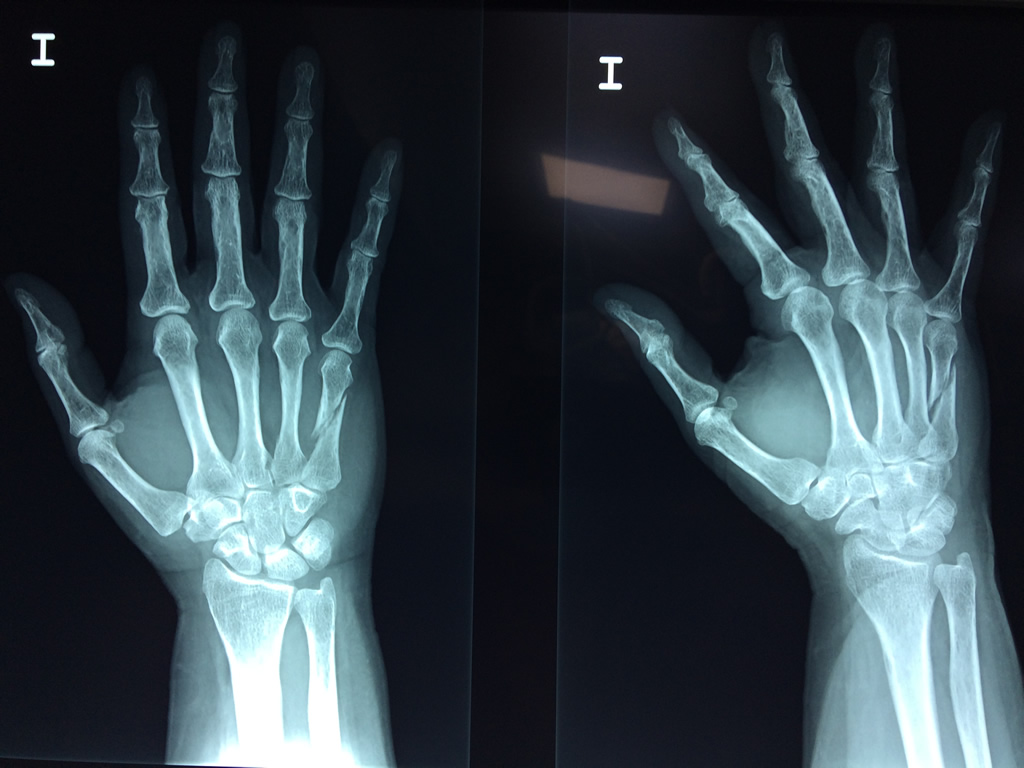

Cirugías de Calcaneo - Cirugías de Muñecas y Manos

Los procedimientos más comunes en cirugía de la mano son aquellos destinados a reparar traumatismos, incluyendo lesiones de tendones, nervios, vasos sanguíneos, y articulaciones; huesos fracturados; y quemaduras, cortes, y otros daños de la piel.